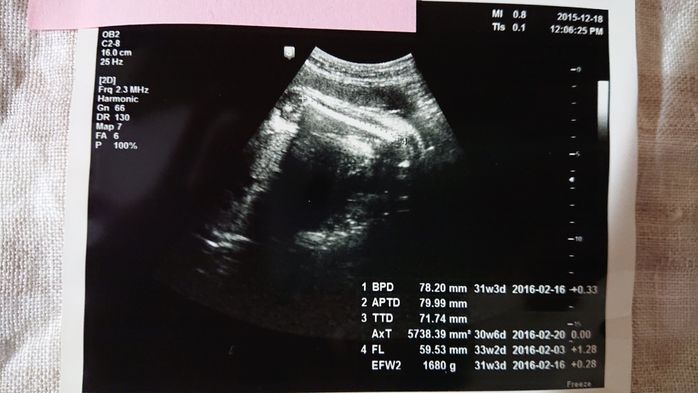

《妊娠30週目のエコー写真》

この写真を撮る2週間程前に切迫早産で入院してしまったのですが、入院してから初めて撮った30週目のエコー写真です。妊娠後期になってくると、赤ちゃんが大きくなりすぎて、ほんの一部しかエコー写真に写らなくなってきました。「赤ちゃんの顔が見たい」と思っても、この日は赤ちゃんの向きが合わずに見ることができませんでした。「赤ちゃんの向きによって、赤ちゃんの顔を見られずに終わってしまう時もある」と、医師に言われて、何だか残念に思ったものです。